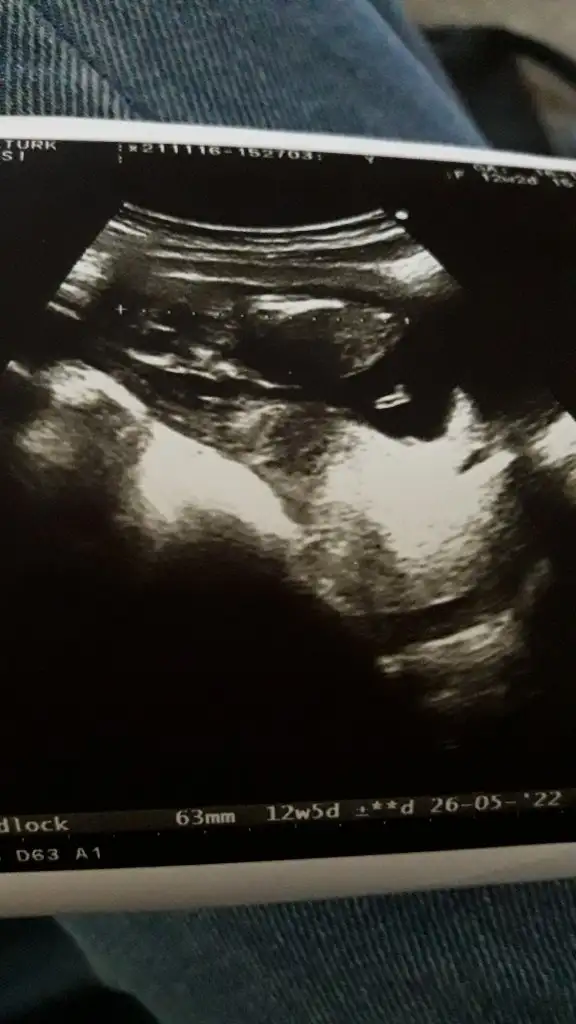

Erkek görünüyorRica etsem tahminde bulunurmusunuz kndini gostrmedi bebegim snra doktor bakti kordon vardı 13+3gunluk ultrason resmi Eki Görüntüle 2951968

Teşekkür ederim canımm sonucu söylerim 3 hafta sonraKız görünüyor

Teşekkür ederim inşallah yanılırsınız :)) öğrenince yazarımErkek görünüyor ama en iyi 11 12 13 haftalar olmalı